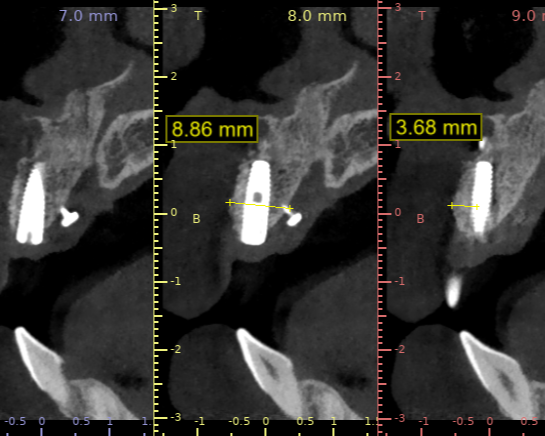

Radiographic Examination

- Findings: Horizontal ridge deficiency consistent with Seibert Class I

Preoperative Virtual Planning

- Implant trajectory indicated full submergence within native bone.

- Anticipated 3 mm crestal dehiscence, with assurance of primary stability.

- Possible Cause of Discrepancy: Poor CBCT quality with wide grayscale range, potentially misinterpreted as bone.